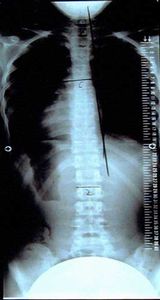

症例11)

体操3ヶ月で15度が計測不能となりました。これが大塚式体操の力

経過

平成18年12月 玉川病院 整形外科受診8歳女子検診15度と診断。

平成19年 1月 大塚整体初診 体操4回指導。

平成19年 3月 再検診へ同病院へ。計測不能。

平成19年 3月 レントゲン持参され本日で終了、自宅体操の継続を指導。

平成18年12月

平成19年3月

15度

計測不能